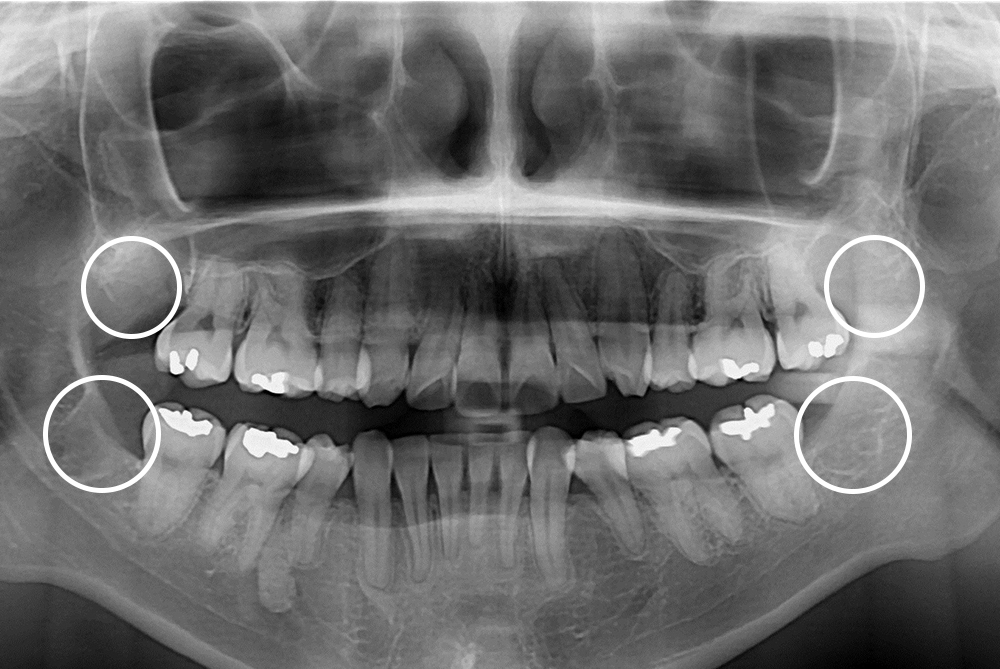

[사랑니] 매복 사랑니 발치

치료후 : 2018-09-18

세종치과는 구강악안면외과학 박사이신 원장님이 발치하는 치과입니다.